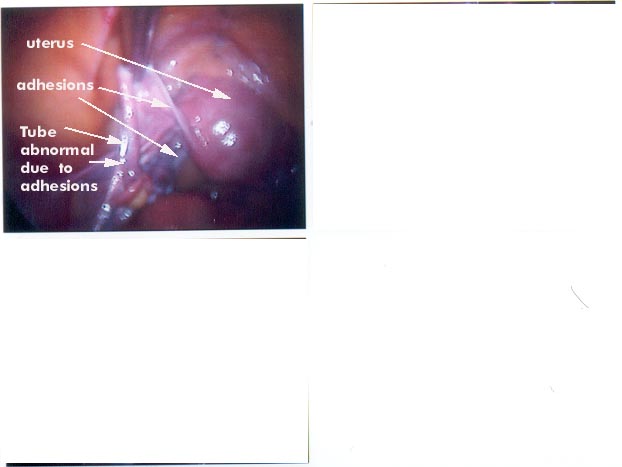

Here are a few photos taken during actual laparoscopic procedures. The photos should be

helpful to explain adhesions.

The following photos will illustrate adhesions.

The next photo was taken during a procedure to seperate (cut) adhesions that occured due

to endometriosis. A cut adhesion band is clearly visible on the uterus.

(Uterus is the scientific name for the womb).